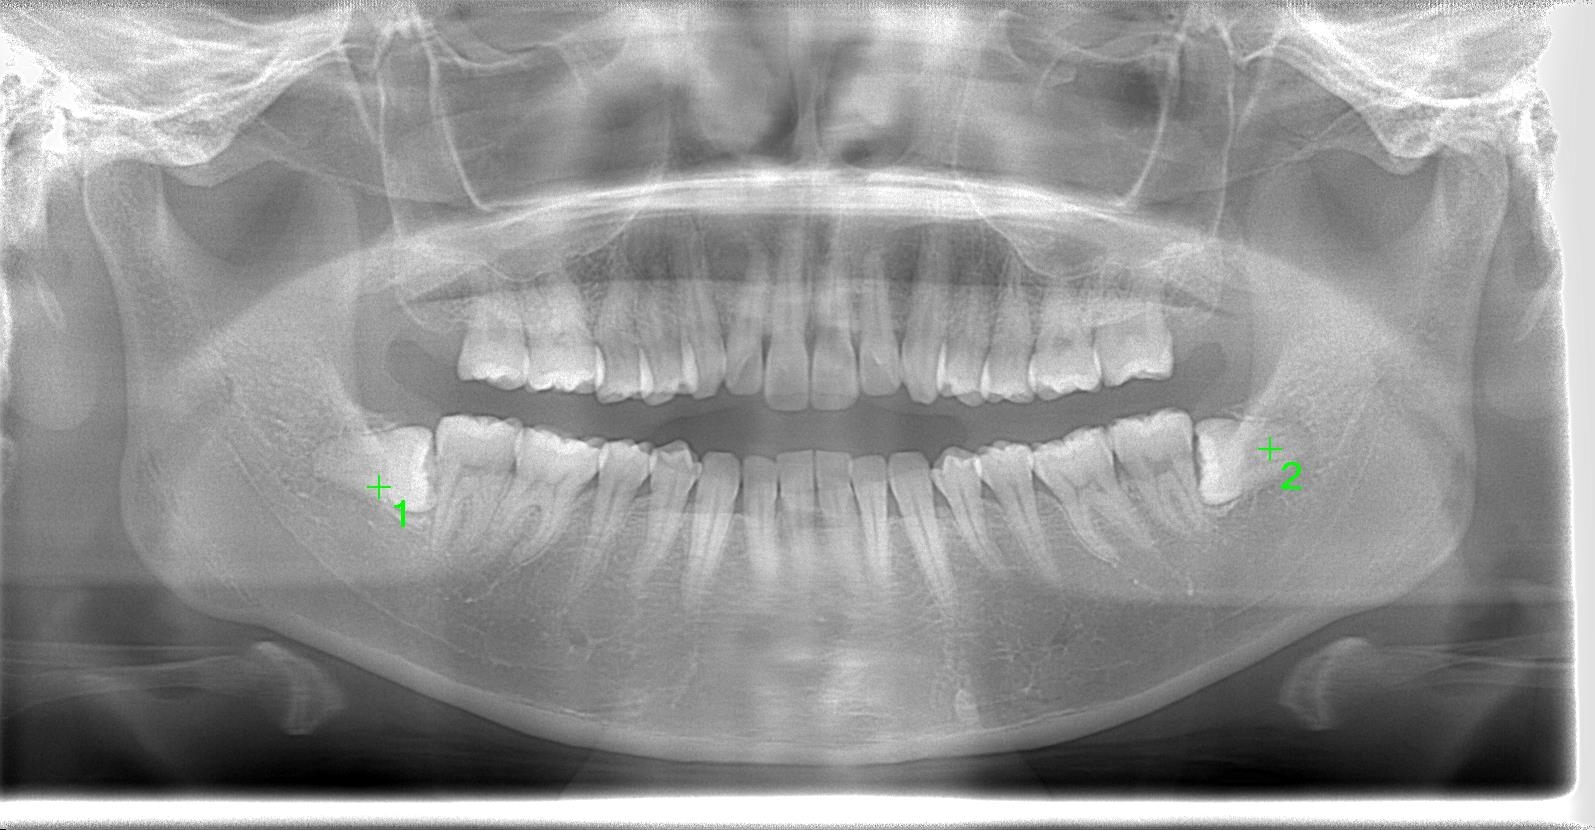

20代前半の女性の親知らず埋伏歯の症例になります。

レントゲン写真の状態を御覧ください。

部位:右下8番埋伏歯

部位:左下8番埋伏歯

術前パノラマ写真

CT画像で状態を確認し、親知らずの歯根の曲がり具合や歯根の太さ、

下の親知らずの場合は下歯槽管神経との距離、

位置関係や骨の厚みなどを確認します。

下歯槽神経を傷をつけないように注意が必要です。

この場合、神経との距離を測り慎重に抜歯しないといけません。